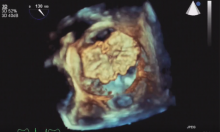

Transcatheter Mitral Valve Techniques: An Update [1]

Neil Moat of the Royal Brompton Hospital in London, UK, discusses current devices for transcatheter mitral valve repair and replacement.